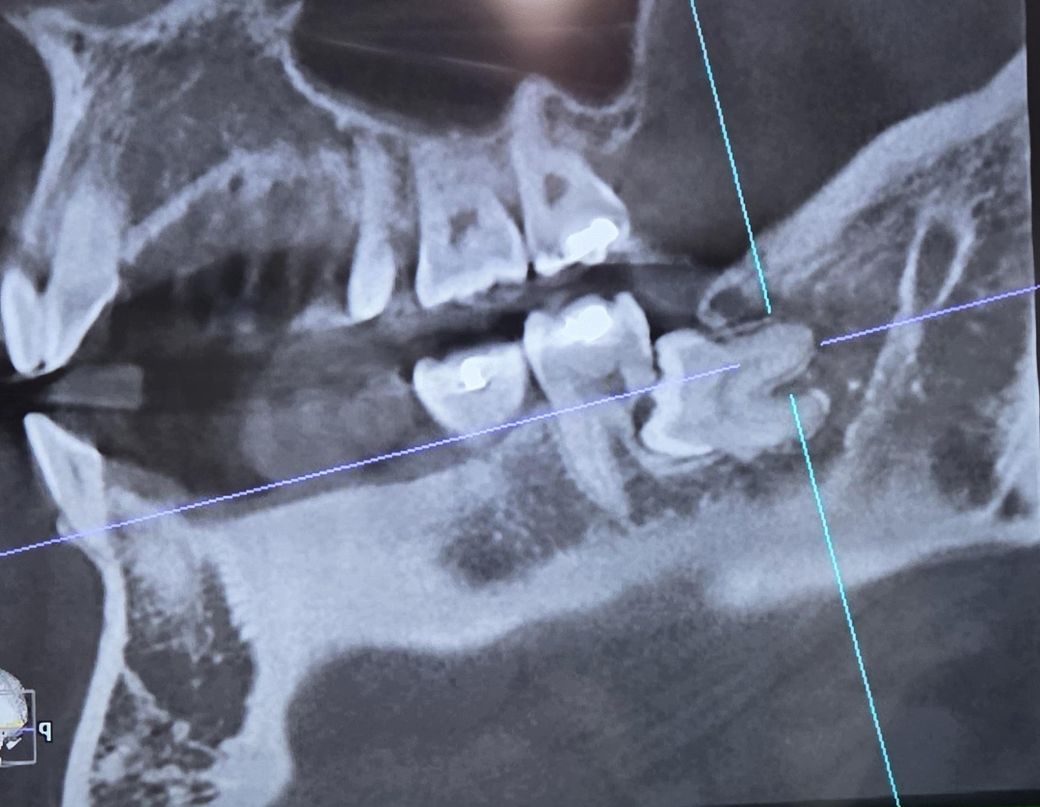

매복사랑니로 인해 어금니 뿌리가 녹았습니다

현재 매복사랑니로 인해 어금니 뿌리가 녹았다 하여 교정 혹은 임플란트를 해야한다고 얘기를 들었습니다

교정으로 충분히 가능한가요? 임플란트도 뼈이식을 해야할수도 있다고 들어서요

치아 뿌리가 사진에 보일정도로 녹은 상태라면 발치를 하고 임플란트를 하시는게 좋을것같습니다.

1. 어떤 의미로 교정치료 이야기를 했을지 모르겠지만 메복사랑니를 견인하여 두번째 어금니 자리로 끌어오는건 쉽지 않을 것 같습니다

2. 지금으로선 두번째 어금니는 빼는것 외에 방법없습니다

3. 사랑니랑 두번째 어금니 빼고 임플란트를 추천합니다

우선 사랑니를 발치하고 난다음에 남아 있는 치아의 상태를 보고 결정을 해도 될것으로 생각됩니다.

큰 문제가 없다면 그냥사용할수도 있지만 불편감이 있거나 염증이 발생한다면 발치후 임플란트를 해야 할수도 있습니다.